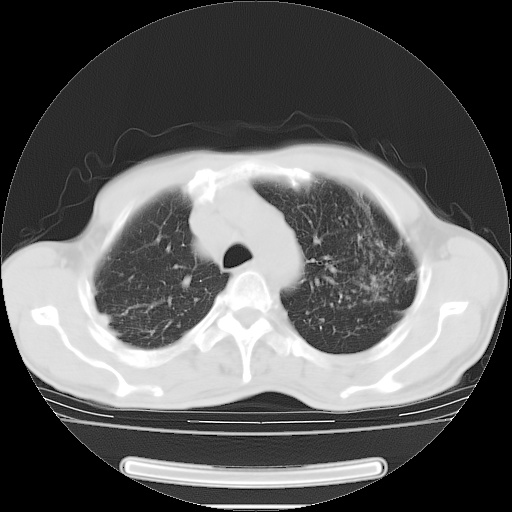

男性患者,63岁。右侧胸背部疼痛2月,加重一周。

考虑:右肺中央型肺癌并右肺下叶不张;两肺尖继发性肺结核。

还有纵隔多处肿大淋巴结及肋骨的改变、两肺多发结节灶。

右肺下叶支气管狭窄闭塞,右下肺不张,气管前间隙淋巴结肿大,两上肺散在分部粟粒灶,沿肺血管支气管束分部,血管支气管束走形较为光滑。考虑右肺中心型肺癌合并肺不张,纵隔淋巴结转移,两上肺癌性淋巴管炎

右肺下叶中心性肺癌并纵隔淋巴结转移,左侧肋骨转移。双肺上叶继发性结核表现。

1)右肺下叶中心性肺癌并纵隔淋巴结转移,两肺转移,左侧肋骨转移。2)双肺上叶继发性结核。